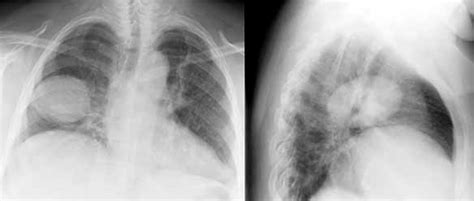

Pulmonary (lung) hamartomas are the most common type of benign lung tumor. Ct of a hamartoma.png 128 × 224; Die umgebende lunge fällt von der gut umschriebenen masse ab, ein typisches merkmal dieser läsionen. Lung hamartoma is the most frequent benign pulmonary tumor and is composed of several types of tissue: On the lateral chest radiograph, there is a nodule seen at the lung base (white arrows) that appears quite dense suggesting calcification.

Current case hamartoma right lower lung diagnosis hidden hamar. Ct of a hamartoma.png 128 × 224;